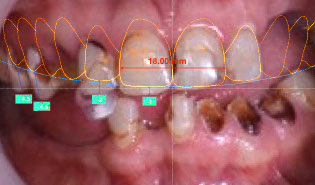

technology allows Brener Clinic to analyse and design the most natural and aesthetic smile makeover

iv) Clinical analysis and digital design of new smile